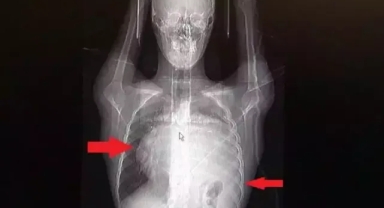

Kalbini 12 santim sağa kaydıran dev tümör doktorlarını bile şaşırttı